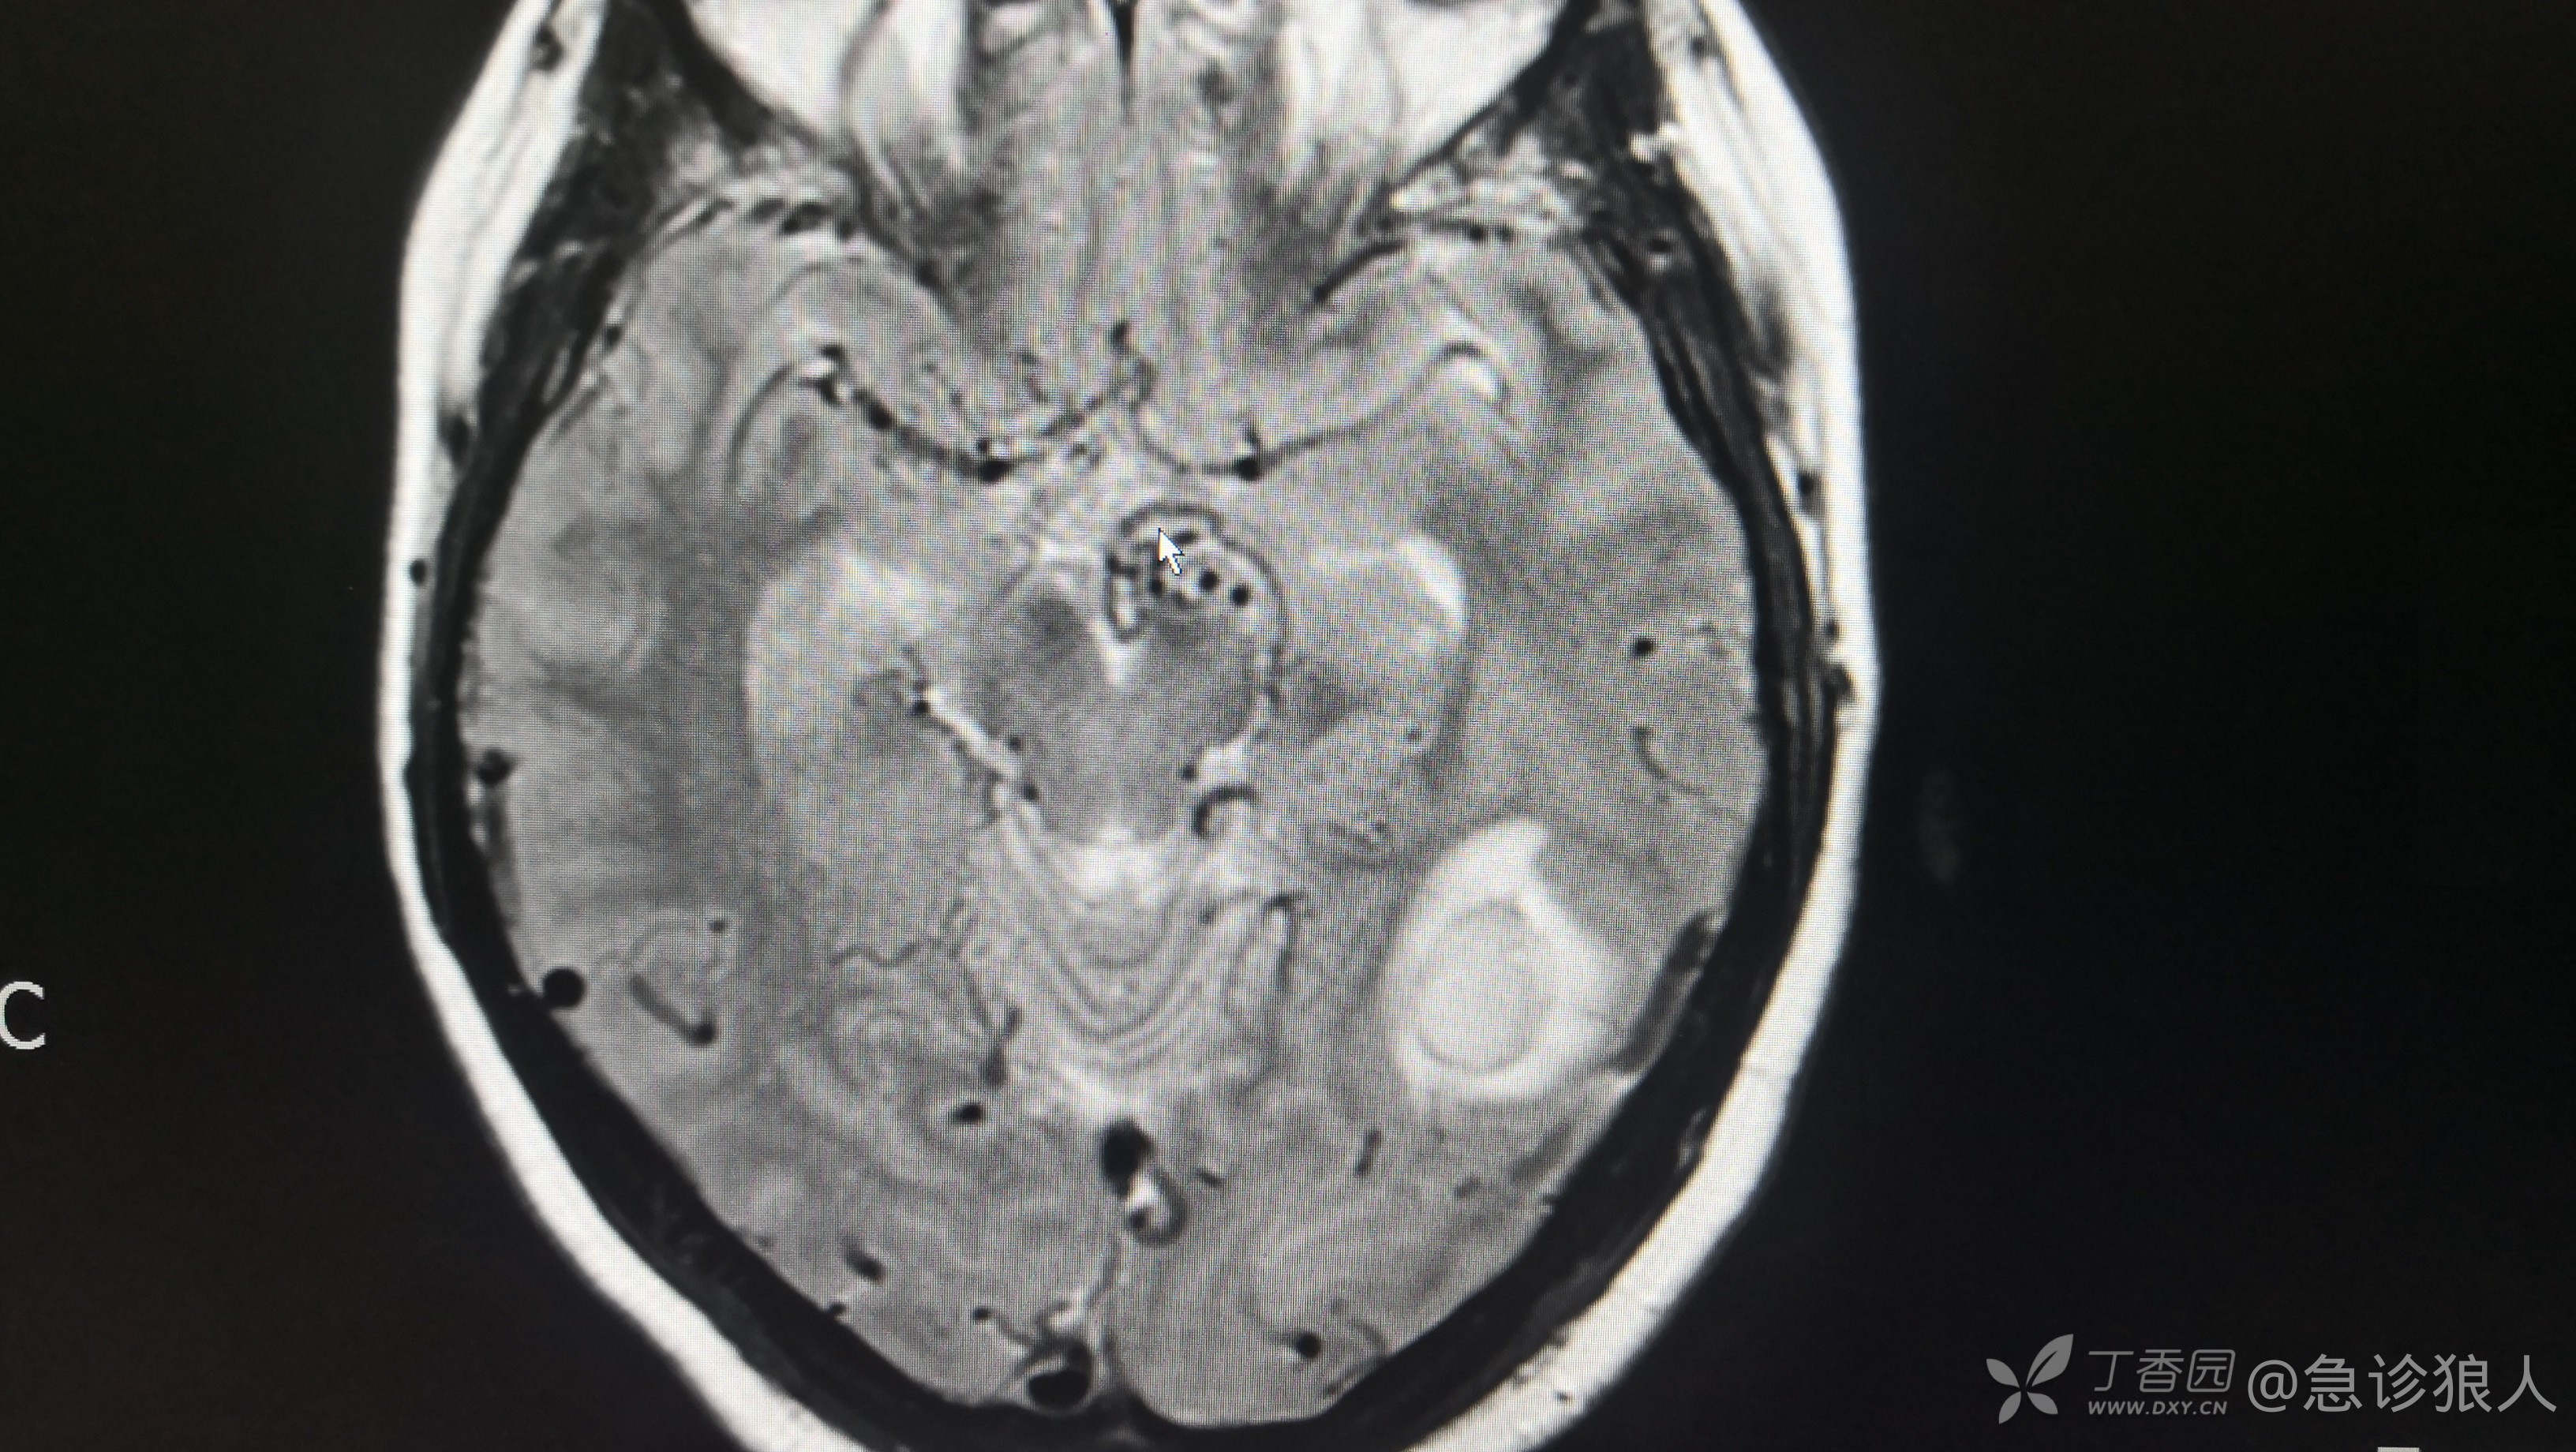

等把影像打开,发现是磁共振报的!

图像如下:

磁共振:1、脑出血(左侧)2、脑血管畸形

这,为啥脑出血CT看不出来,我又反复看了ct确实看不出来。

左侧大脑半球多发杂乱,迂曲血管影,与左侧乙状窦相通,考虑硬脑膜动静脉瘘可能性大。